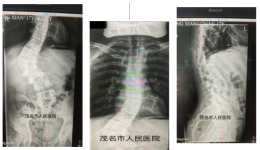

• 我院脊柱外科成功开展3D打印技术辅助脊柱侧弯矫形术

我院脊柱外科成功开展3D打印技术辅助脊柱侧弯矫形术

近日,我院脊柱外科在中国人民解放军南部战区广州总医院丁焕文教授的细心指导,联合医院麻醉手术科团队,顺利完成粤西首例脊柱先天型畸形三维精准矫形内固定术。3个月前,17岁的小周发现自己脊柱畸形,向右侧弯曲,腰部活动以及抬腿动作受限,严重...